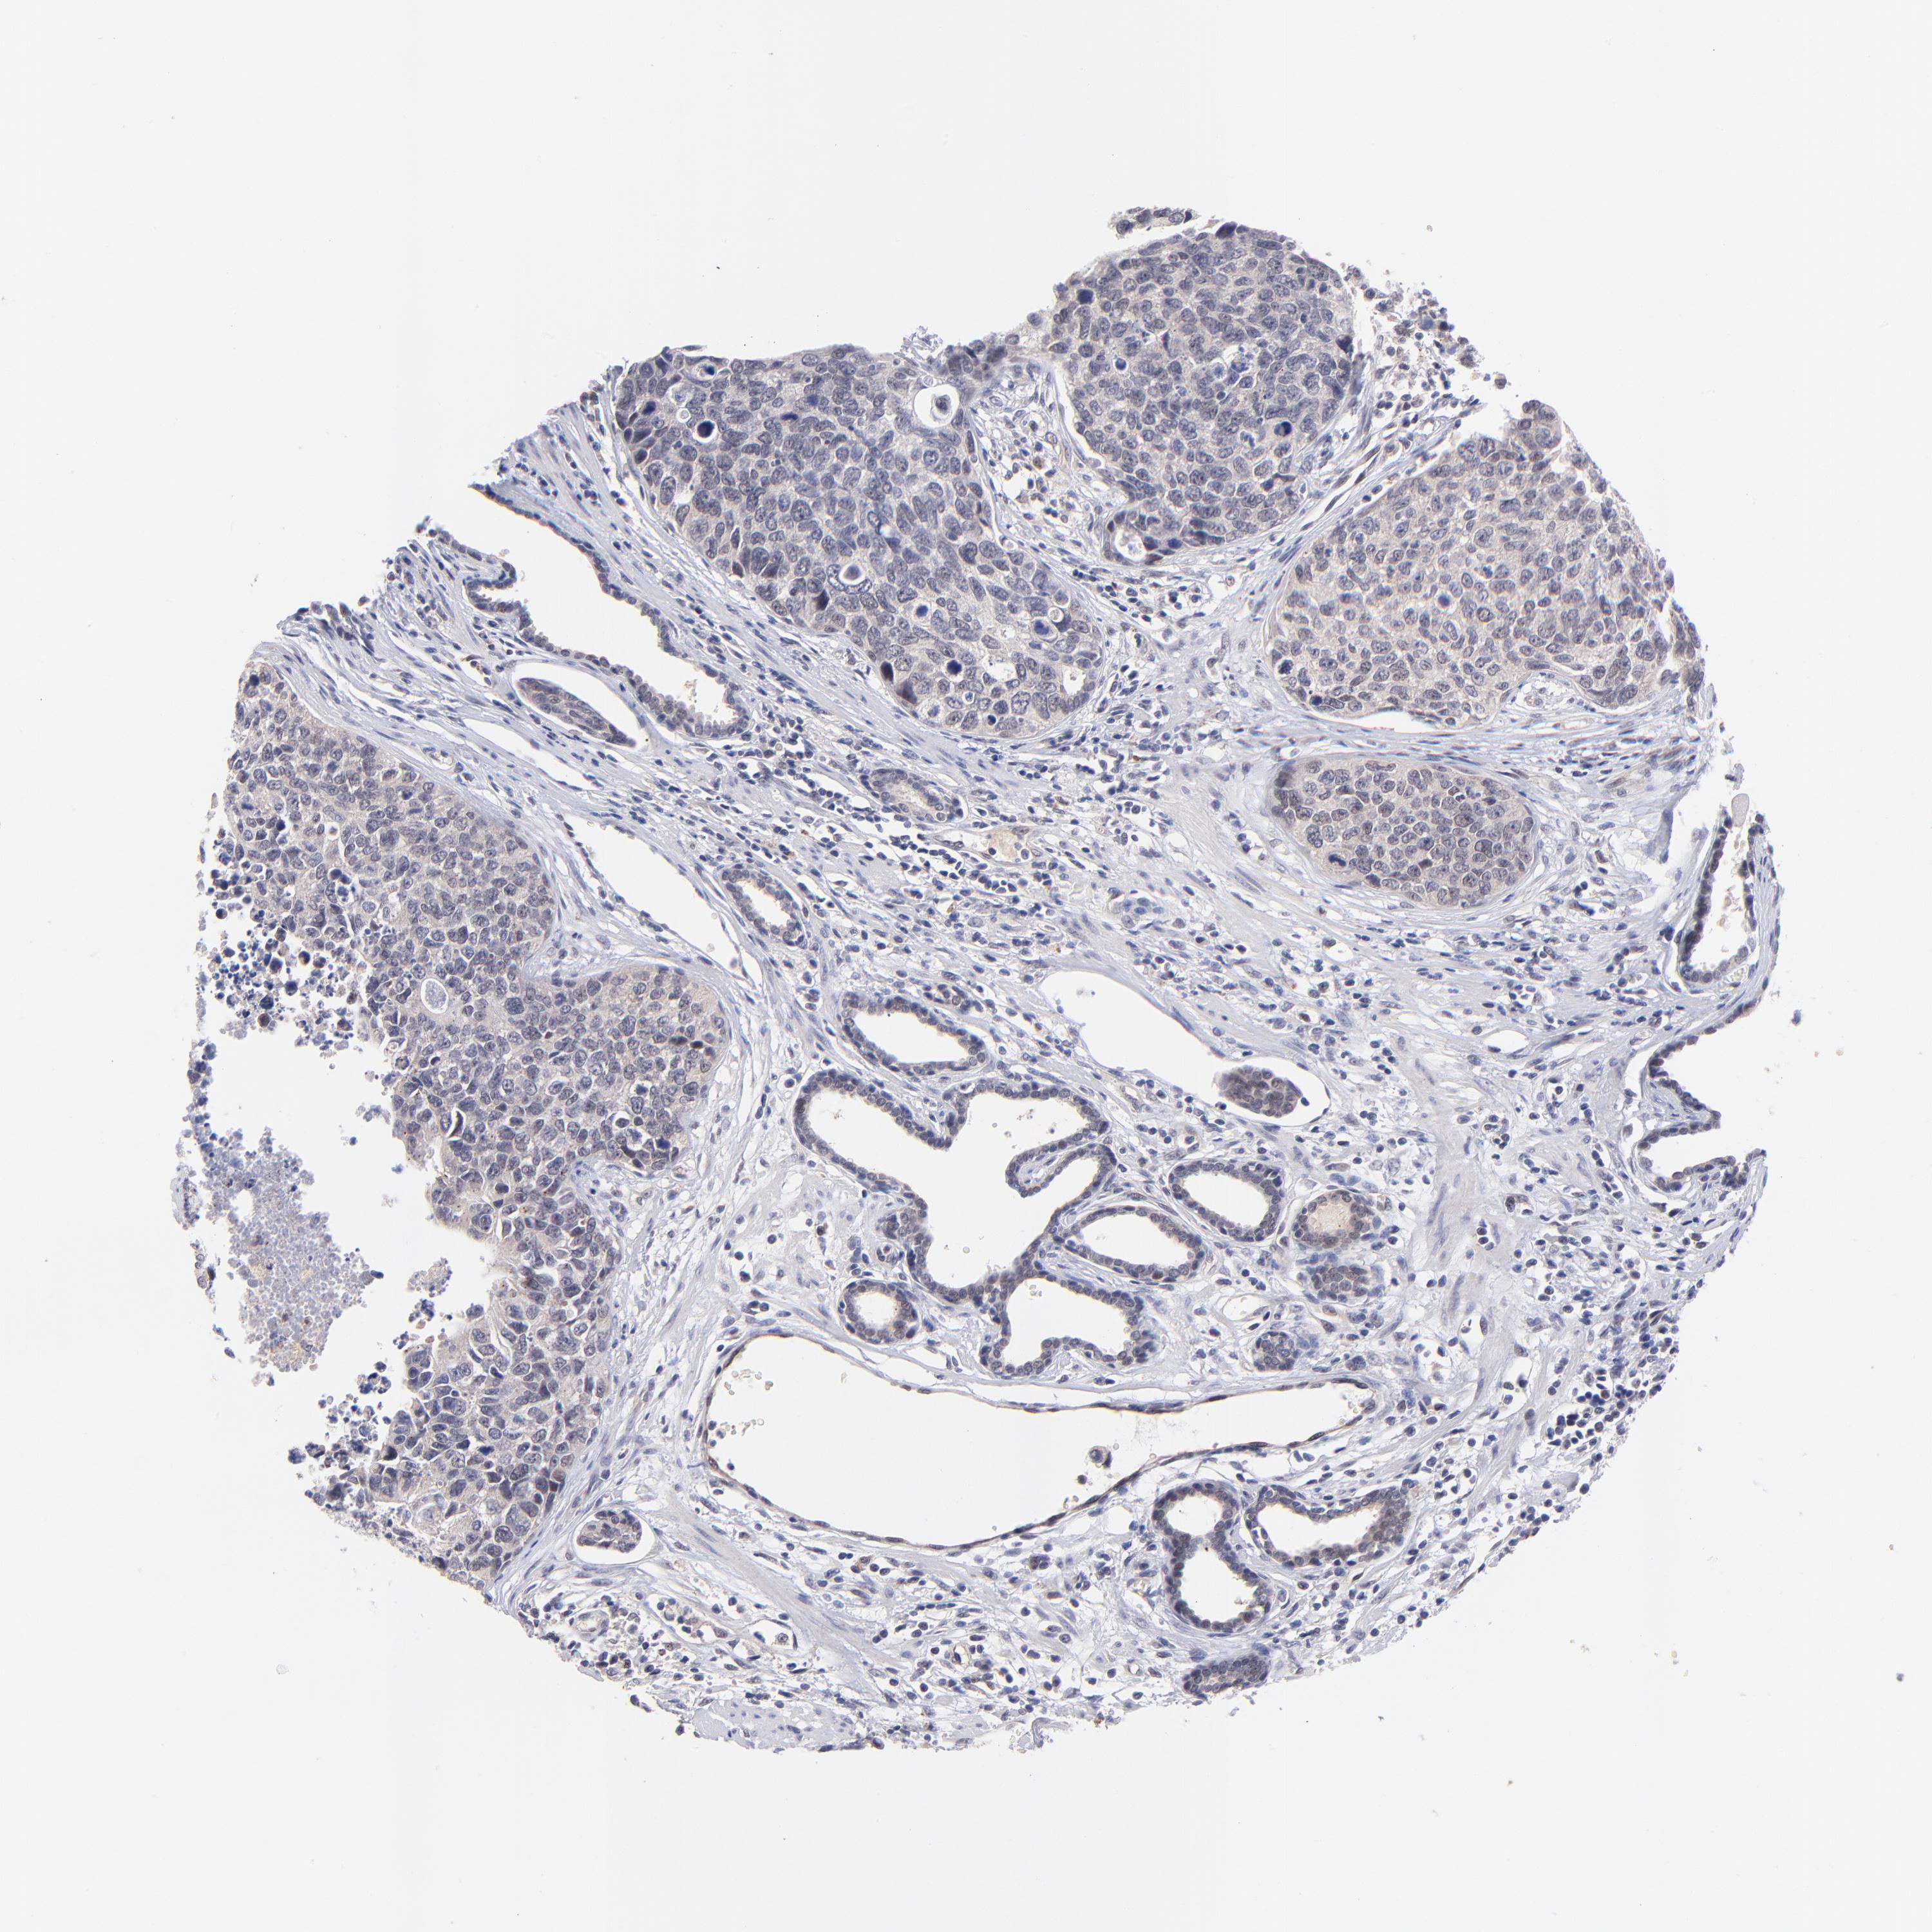

UROTHELIAL CANCER - Protein expressioni

A mouse-over function shows sample information and annotation data. Click on an image to view it in a full screen mode. Samples can be filtered based on level of antibody staining by selecting one or several of the following categories: high, medium, low and not detected. The assay and annotation is described here.

Antibody stainingi

Antibody staining in the annotated cell types in the current human tissue is reported as not detected, low, medium, or high, based on conventional immunohistochemistry profiling in selected tissues. This score is based on the combination of the staining intensity and fraction of stained cells.

Each image is clickable and will lead to virtual microscopy that enables deeper exploration of all samples and also displays staining intensity scores, fraction scores and subcellular localization as well as patient and tissue information for each sample.

Antibody HPA003203

Staining

High

Medium

Low

Not detected

Intensity

Strong

Moderate

Weak

Negative

Quantity

>75%

75%-25%

<25%

None

Location

Nuclear

Cytoplasmic/membranous

Cytoplasmic/membranous,nuclear

Urothelial carcinoma, Low grade